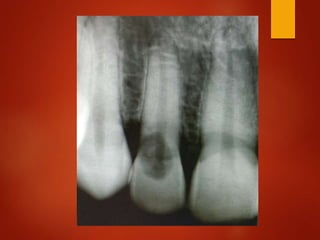

El documento es un registro médico odontológico que muestra las fechas de las visitas de un paciente al centro de salud El Raval, incluyendo exámenes y tratamientos realizados como la extracción de cálculos salivales en abril y mayo de 2012.